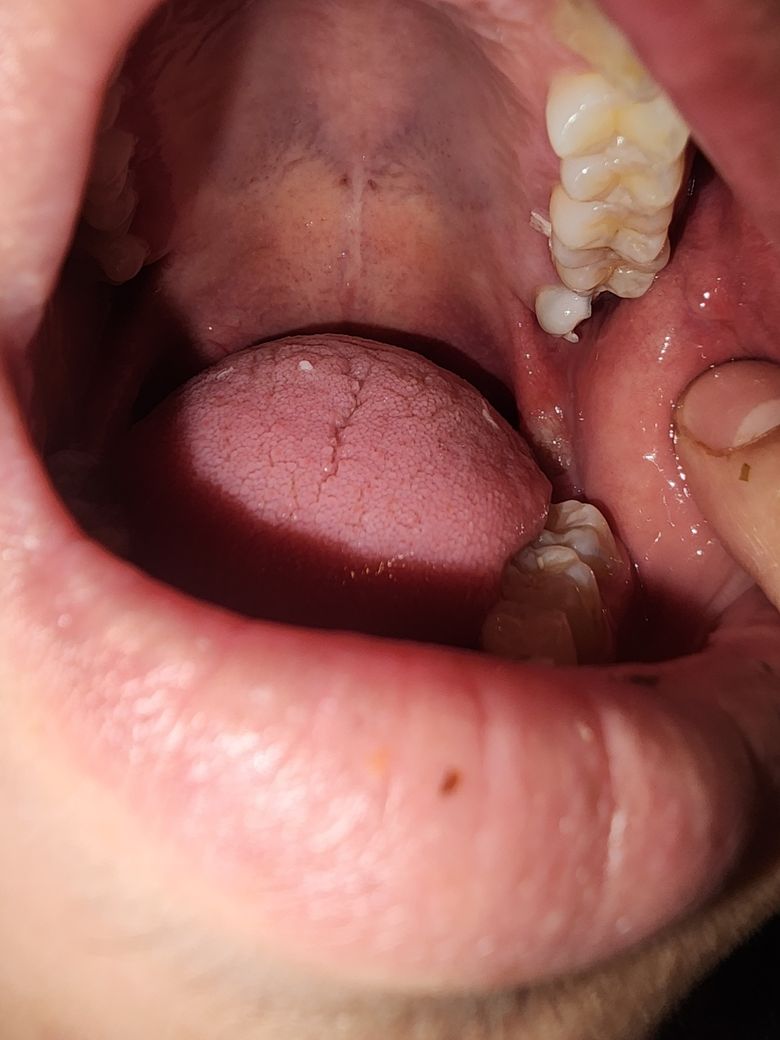

입안에 생긴게 뭐에요??!!급해요

입안에 뭔가 생겼는데 혹시 궤양일수도 있나요 ㅠㅠㅠㅠ살짝 딱딱한거같아요 아프고 따가워요 ㅠㅜ도와주세요 뭐라설명해야할지 모르겠어요 ㅠㅠㅠㅠㅠ

사진으로는 정확한 확인이 힘들어 보입니다 하지만 구강 내에 구내염이 생기게 되면 해당 부위에 통증이 있을 수 있습니다 구내염이 생기는 원인은 몸의 면역력이 떨어지게 되었을 때 점막이 손상이 생기게 되면 감염이 되면서 생기게 됩니다 결과적으로 몸의 면역력이 높아져야지 해당 문제가 해결되기 때문에 충분한 휴식을 취해 주는 것이 좋습니다

• 안녕하세요 치과의사 김철진입니다. 저부위는 아마도 치아에 볼살이 씹히면서 생긴 상처 같습니다. 시간이 지나면 괜찮아 질테니 너무 걱정하지 않으셔도 될것같습니다.

• 그냥 구내염이 생긴 것으로 보입니다.

구내염은 약 일주일 이내에 소실될 가능성이 높으며 약국에서 오라메디같은 약사서 바르면 잘 낫습니다